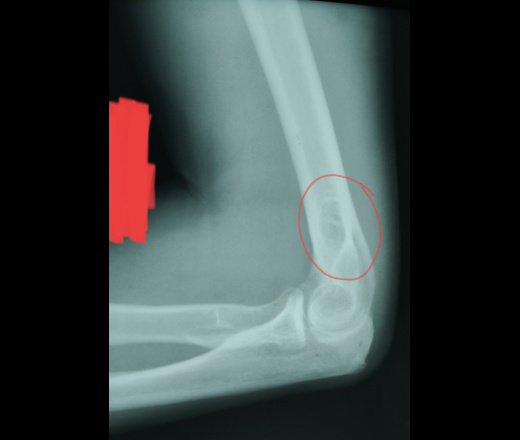

Мужчина, 48. Жалобы на боли в правом локтевом суставе. Травм не было. Работа связана с физическим трудом.

На боковом снимке смущается обведенный округлый участок. На прямом ничего страшного не вижу. Суммация или всё-таки можно заподозрить образование?

На мой взгляд - нормальное строение